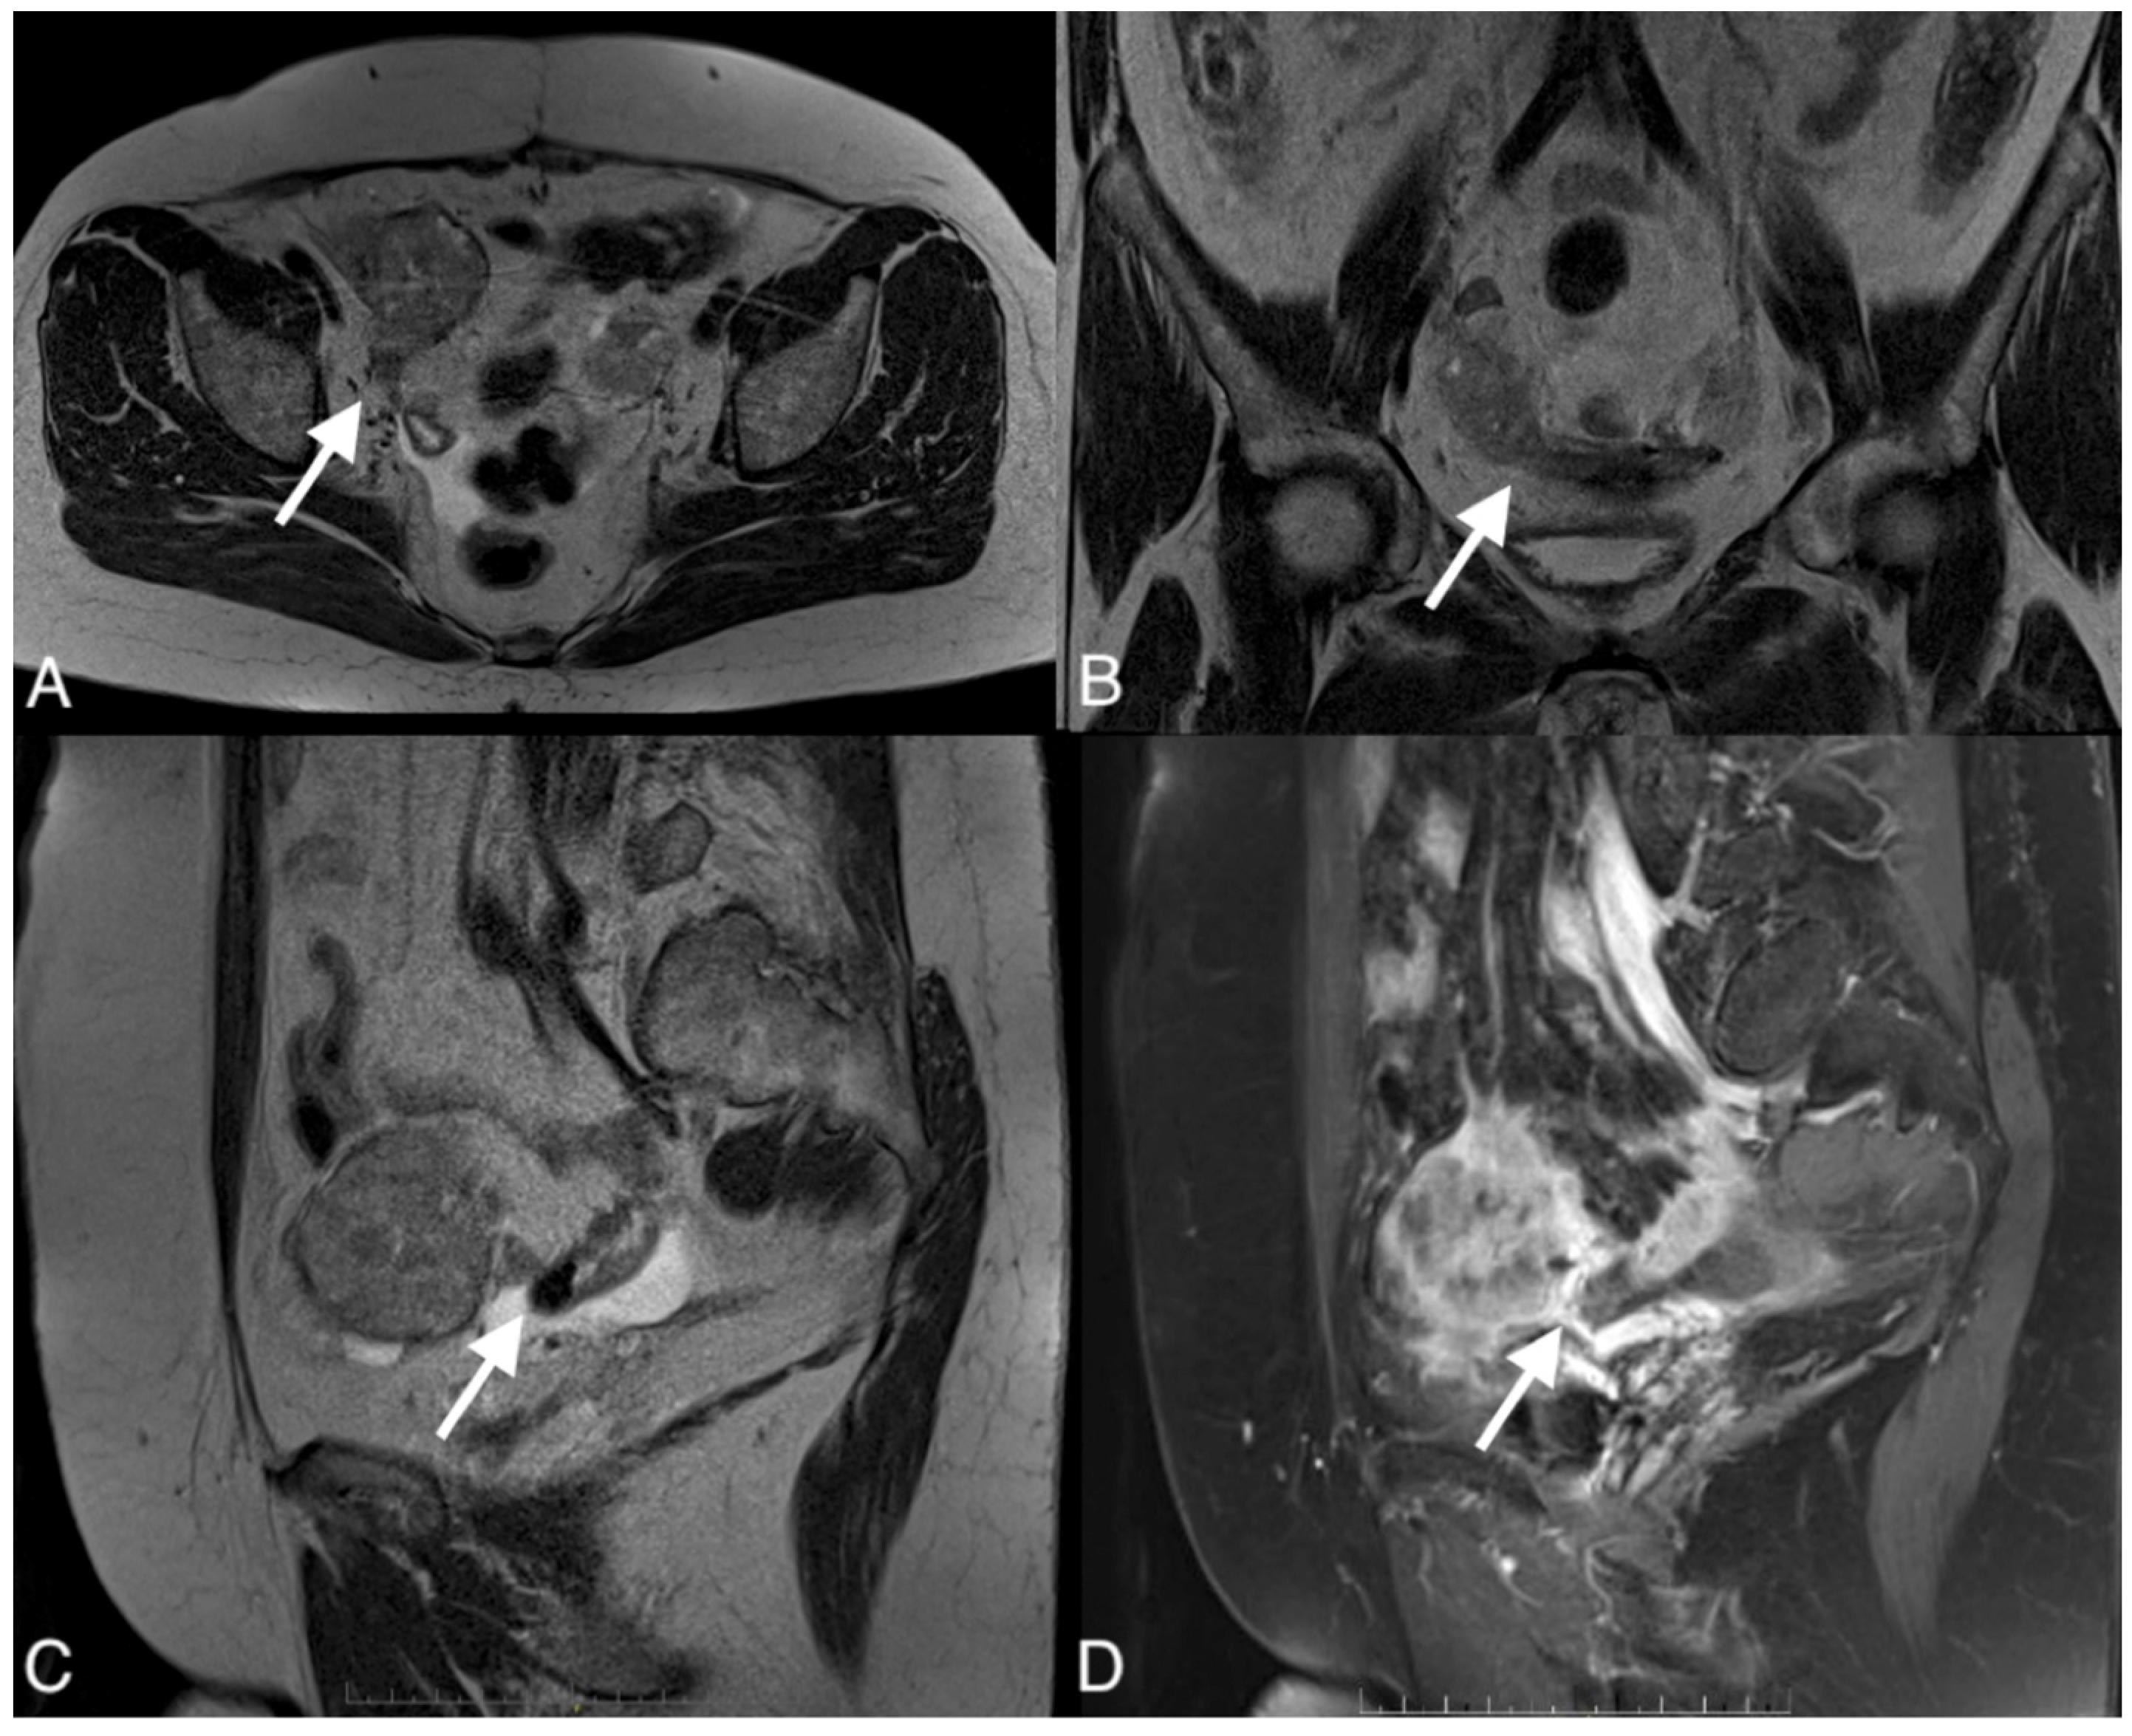

Figure 2.

Images of a 54-year-old patient with an ovarian cancer recurrence in the form of the fistula between the tumor and rectum. CT obtained in the coronal (A), sagittal (B), and axial plane (C) shows large pelvic tumor with adjacent rectum.

The median diameter of the relapsed tumor was 89 mm (range 36–130 mm). In all cases, fistulas formed between the tumor and large bowel. In three cases, fistulas formed between the rectum, including two between the sigmoid colon, one sigmoid and descending colon, one between the cecum and ascending colon, and one between the sigmoid colon and left ureter. On CT, in all cases, the fistulas were not directly visible, with only indirect signs of the fistula observed, such as infiltration of the intestine by the tumor, which we observed as vanishing of the fatty tissue between the tumor and the description of the intestinal wall, disruption of the intestinal wall, or the presence of gas in the tumor. In five patients, we observed thickening of the intestinal wall associated with a fistula (Figure 1, Figure 2 and Figure 3).